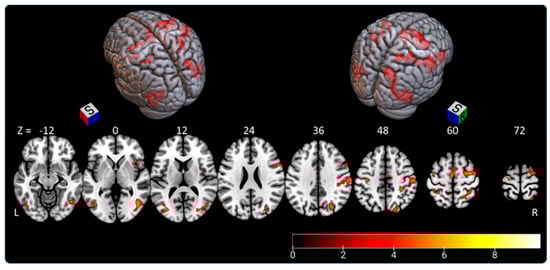

3.2. Subjective Longitudinal Body Plane Task (SLB)

- the right parietal lobe (superior parietal lobule: A7r, A7c, A5l, A7pc, A7ip; inferior parietal lobule: A39c, A40rd, A40rv; precuneus: dmPOS; postcentral gyrus: A1/2/3ulhf, A2, A1/2/3tru), representing 27% of activated areas;

- the right lateral occipital cortex (V5/M+, msOccG, lsOccG, mOccG, iOccG), representing 22.5% of activated areas;

- the right frontal lobe (predominant in the precentral gyrus: A4hf, A6cdl, A4ul, A4tl, A6cvl; superior frontal gyrus: A8m, A6dl, A6m; inferior frontal gyrus: A44d, A44op; paracentral gyrus: A4ll), representing 21% of activated areas;

- the left lateral occipital cortex (V5/MT+, mOccG, iOccG), representing 8% of activated areas;

- the left frontal lobe (supplementary motor area: A6m; precentral gyrus: A4hf, A6cdl, A4ul, A4t; and paracentral lobule: A4ll), representing 7.5% of activated areas; and

- less than 5% in each of the following areas: left parietal lobe (superior parietal lobule: A5l, A7pc; inferior parietal lobule: A39c, A39rv; postcentral gyrus: A1/2/3ulhf, A2), right insular lobe (vIa, dIa, dIg, dId), left temporal lobe (middle temporal gyrus: A37dl; inferior temporal gyrus: A37vl; fusiform gyrus: A37lv), left cingulate gyrus, right temporal lobe (middle temporal gyrus: A37dl; inferior temporal gyrus: A37vl; fusiform gyrus: A37lv), and right cingulate gyrus.

| Cluster Voxels/Side | AAL3 % in the Area | Peak MNI Coordinates (x y z)/T Value | Brainnetome % in the Area |

|---|---|---|---|

| 565/right | 25.3 occipital mid 25.1 temporal mid 18.9 occipital sup 13.3 temporal inf | 44 −66 −6/10.448 | 16.6 mOccG 9.7 msOccG 8.5 lsOccG 38.1 V5/MT+ |

| 512/right | 59.4 postcentral 16.8 supramarginal 15.0 parietal sup | 50 −22 42/6.4996 | 18.8 A2 24.2 A40rd 15.4 A5l 11.1 A40rv |

| 240/right | 64.6 frontal sup | 36 −6 58/6.921 | 56.3 A6cdl |

| 15.0 precentral 11.3 frontal mid | 22.5 A6dl | ||

| 218/left | 59.2 occipital mid 20.2 temporal mid 18.4 occipital inf | −34 −78 10/6.0758 | 19.7 mOccG 45.4 V5/MT+ 11.0 A39c |

| 152/right-left | 59.9 supp motor area L 31.6 sup motor area R | −4 −12 58/6.0816 | 51.3 lA6m 26.3 rA6m |

| 107/right | 60.8 frontal inf oper 39.3 precentral | 58 12 30/6.2155 | 92.5 A6cvl |

| 78/right | 87.2 insula | 44 20 −6/5.5758 | 34.6 dla 44.9 dld 11.5 A44op |

| 55/left | 98.2 precentral | −40 −10 66/5.086 | 45.5 A6cdl 29.1 A4hf 18.2 A4ul |

| 52/left | 73.1 postcentral 26.9 parietal sup | −40 −44 62/4.699 | 36.5 A7pc 38.5 A5l 19.2 A2 |

| 45/right-left | 53.3 cingulate mid L 31.1 cingulate mid R 11.1 sup motor area L | −2 6 42/6.001 | 57.8 lA24cd 35.6 rA24cd |

| 31/left | 51.6 postcentral | −38 −18 46/5.1726 | 38.7 A1/2/3ulhf |

| 48.4 precentral | 41.9 A4hf |